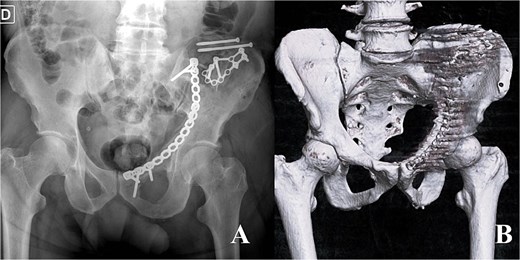

A 58-year-old male presented following a 3-meter fall, with an isolated ABC acetabular fracture of the right side (Fig. 1). Surgery was performed 2 days after the injury using an anterior pelvic approach via the Pfannenstiel incision combined with the first window of the ilioinguinal approach. Fixation began with the iliac crest using 4.5 mm cannulated screws to anchor the constant fragment, followed by a calcaneal plate to address comminution of the iliac wing, and a reconstruction plate for the anterior column (Fig. 2). As the posterior components were well-aligned post-fixation, a posterior approach was deemed unnecessary. Post-operative after 24 months radiographs and TC demonstrated anatomical reduction with no signs of implant failure (Fig. 3), just as shown in the TC comparison (Fig. 4). The physical exam presents a satisfactory range of motion (Fig. 5). Pain, function and quality of life outcomes were assessed using the Visual Analog Scale (VAS), Majeed Pelvic Score, and SF-12 up to 24 months post-operatively, respectively. The results are summarized in the following table (Table 1) and graphic (Fig. 6).

Radiograph immediate postoperative (A) and CT immediate postoperative (B).